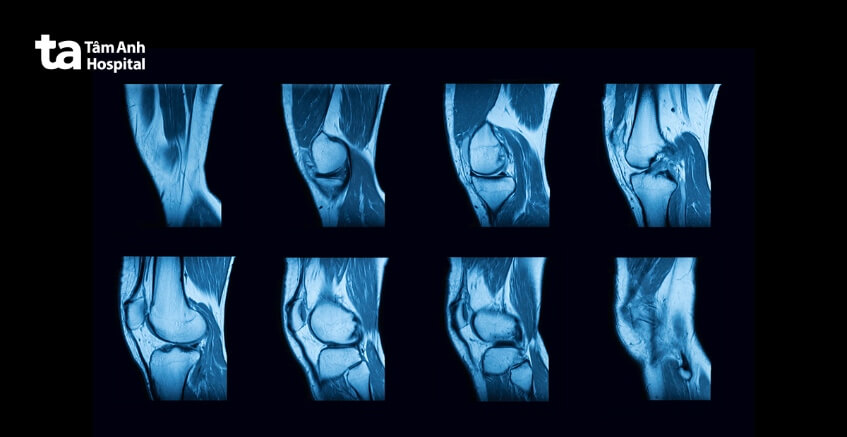

Chụp cộng hưởng từ (MRI): Bác sĩ cũng có thể chỉ định cho người bệnh chụp MRI để xem liệu có vật gì đè lên dây thần kinh không, ví dụ như khối u hay đĩa đệm thoát vị.

Chụp cộng hưởng từ (MRI) đôi khi được áp dụng để hỗ trợ bác sĩ chẩn đoán bệnh viêm thần kinh ngoại biên